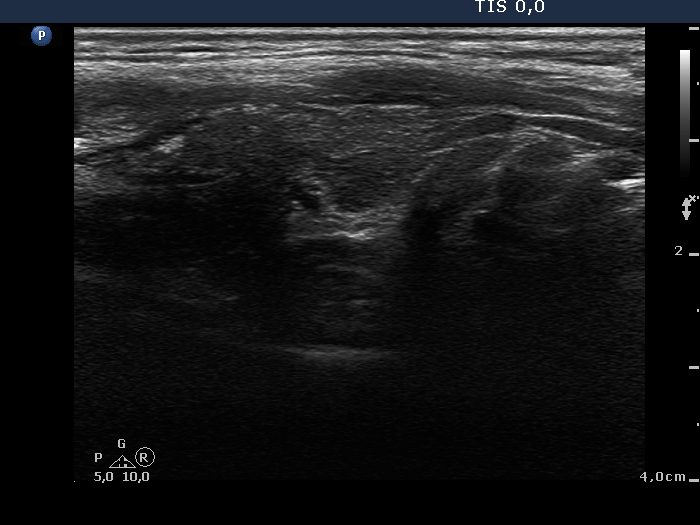

Subacute granulomatous de Quervain's thyroiditis - Case 43.

14 months after initial investigation (ultrasonographic picture 5)

Left lobe, longitudinal view.